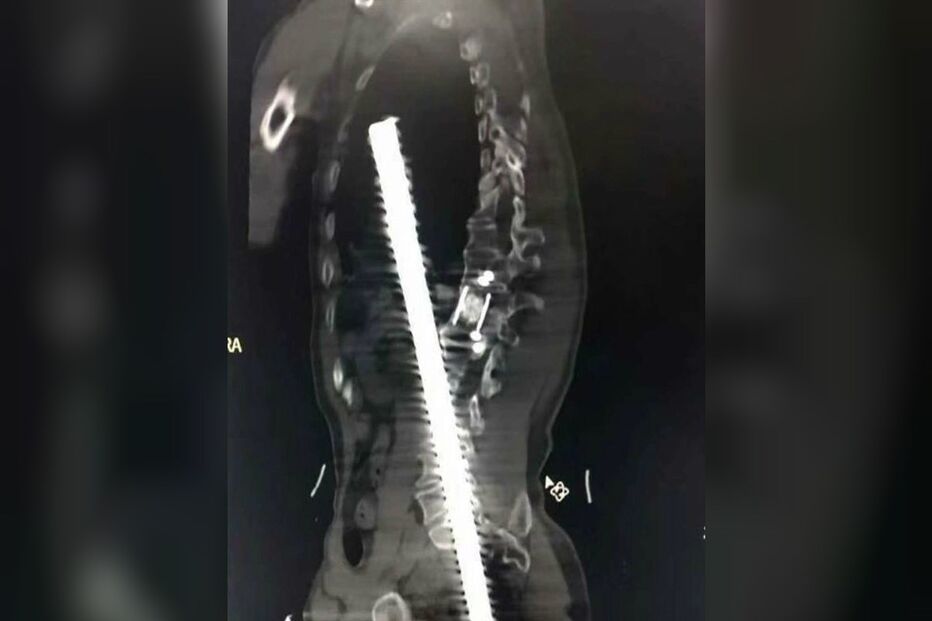

As radiografias mostram a gravidade das lesões. O homem empalado foi operado de urgência e conseguiu sobreviver, dado que, com muita sorte, a barra não atingiu nenhum órgão vital.

O médico que o operou, Zhang Jianwen, revelou que cerca de 61 cm dos 80 cm da barra de aço reforçado entraram no corpo do operário. Os bombeiros tiveram de cortar a barra de aço para levar o homem para o hospital, onde foi submetido a uma operação de seis horas.